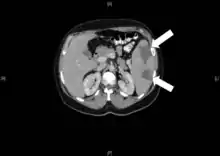

Инфа́ркт (лат. infarcire «начинять, набивать») — омертвление (некроз) органа или ткани вследствие острого недостатка кровоснабжения[1][2]. Причины инфаркта: тромбоз, эмболия, длительный спазм артерий и функциональное перенапряжение органа в условиях гипоксии[1].

Виды инфаркта по форме[1]:

- Клиновидная форма. Специфична для селезёнки, почки, лёгкого.

- Неправильной формы. Встречается в сердце, и головном мозге (ишемический инсульт, инфаркт таламуса).